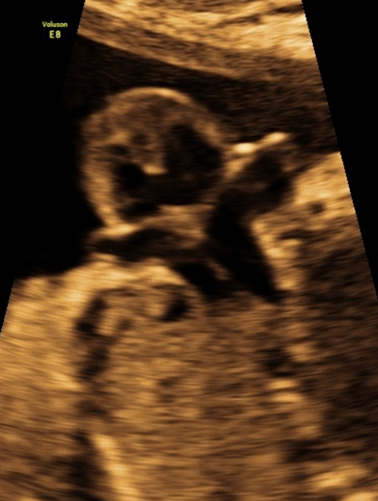

产科_胎心_主动脉弓切面